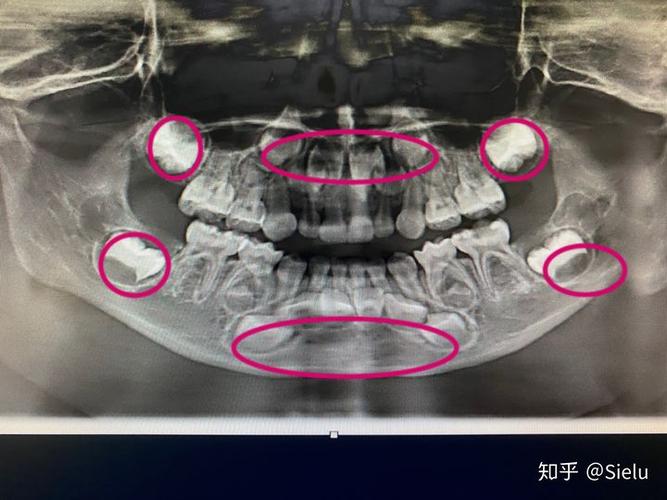

5岁的小朋友,画圈的是恒牙胚

恒牙牙胚埋藏在乳牙根下,尚未发育完全如果确定恒牙近期不会萌出